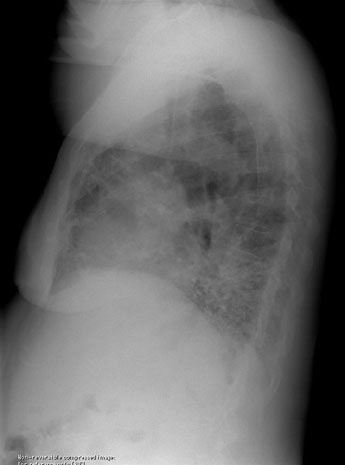

This middle aged patient presented with complaints of hemoptysis. The chest radiographs demonstrated branching tubular densities within the left lower lobe- the finding was better appreciated over the spine on the lateral view (arrow below), but can also be seen on a magnified image of the PA exam. Branching tubular densities are sometimes referred to as the "finger-in-glove" appearance of mucous filled dilated bronchi. Click here to view the patients CT scan.

Lateral: